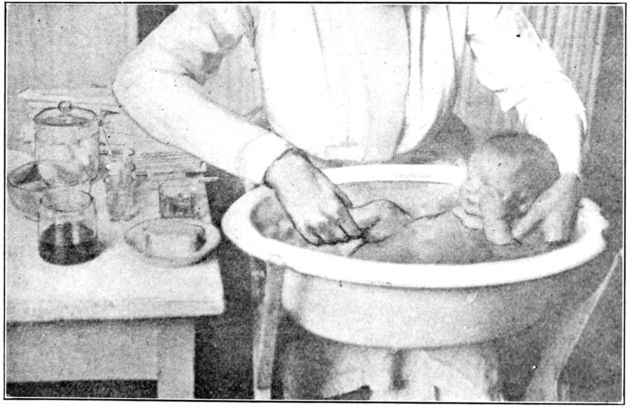

| 154. | Bathing the baby | 467 |